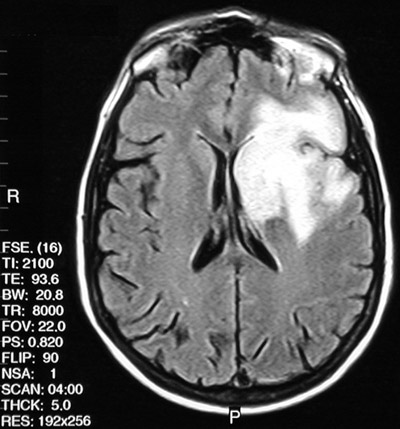

![]() | The axial T2 weighted FSE MRI scan above and the FLAIR MRI scan below both demonstrate an area of enhancement involving primarily the left frontal white matter. There was also extension to basal ganglia, thalamus, and portions of the temporal and parietal lobes in this case of progressive multifocal leukoencephalopathy (PML). Note the relative sparing of the overlying cortex seen best in the FLAIR scan below. |